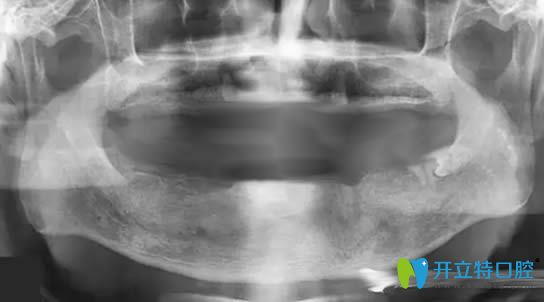

帶10年活動(dòng)假牙萎縮的牙槽骨圖片

但好景卻不長(zhǎng),在2025年的時(shí)候,總出現(xiàn)黏膜潰瘍等牙周病,我讓反復(fù)的到口腔進(jìn)行治療......讓我的飲食成了的問題。為了改善現(xiàn)狀,孩子帶我去了一家私人牙科進(jìn)行咨詢,說我佩戴活動(dòng)假牙時(shí)間長(zhǎng)了,造成了牙槽骨低平,無法讓活動(dòng)義齒取得好的固位,并且,就連做種植牙的基礎(chǔ)條件都沒有了......

牙槽骨萎縮全景片